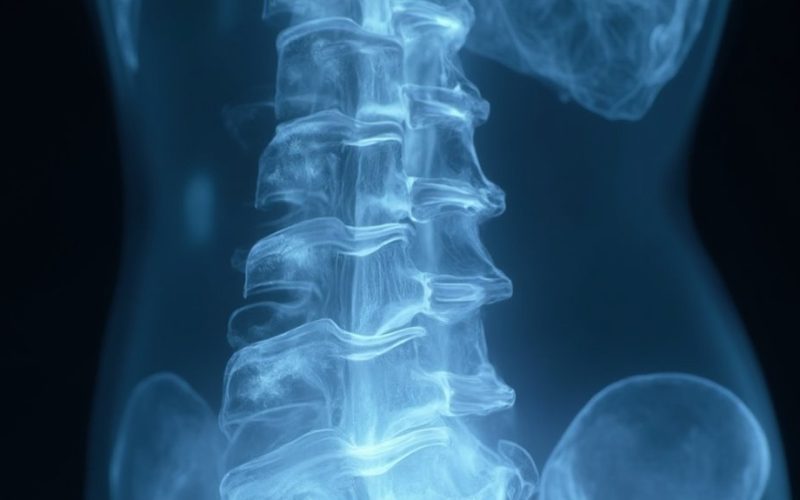

Nors dažnai nepastebima, stuburo degeneracija apima sudėtingus biocheminius ir biomechaninius procesus, kurie palaipsniui pažeidžia tarpslankstelinių diskų vientisumą ir nervų funkciją. Jūs patiriate mikroskopinius pokyčius, kurie kaupiasi nejučia, sutrikdydami ląstelių matricos sudėtį ir uždegiminio atsako mechanizmus.

Uždegiminiai citokinai, tokie kaip TNF-alfa ir IL-6, spartina disko matricos irimą, o oksidacinis stresas sukelia mitochondrijų disfunkciją stuburo audiniuose. Šiems degeneraciniams pokyčiams būdingas kolageno tinklo suirimas, sumažėjęs proteoglikanų kiekis ir sumažėjęs vandens sulaikymas. Svarbiausias vaidmuo tenka ląstelių senėjimui, kai senstančios ląstelės išskiria uždegimą skatinančias signalines molekules, kurios dar labiau pažeidžia struktūrinį vientisumą.

Mechaninės apkrovos modeliai, genetiniai polinkiai ir gyvenimo būdo veiksniai dinamiškai sąveikauja, sukurdami sudėtingą aplinką, kurioje stuburo audinių atsparumas palaipsniui mažėja. Šių sudėtingų mechanizmų supratimas tampa labai svarbus kuriant tikslines intervencines priemones, skirtas su amžiumi susijusiam stuburo būklės blogėjimui sušvelninti.